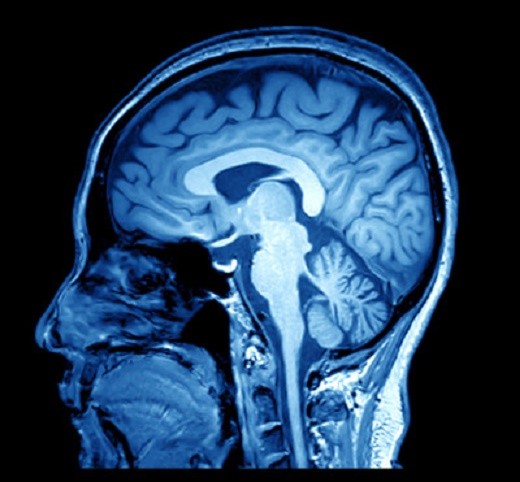

نوروسافاری | آسیب وارد شده به مغز اغلب موجب از دست دادن حس بویایی می شود که می تواند برای یک دوره زمانی کوتاه یا بلند مدت باقی بماند. به طور ویژه، آسیب دیدن لوب فرونتال مغز، جایی که بو پردازش می شود، می تواند به از دست دادن حس بویایی منجر شود.

آسیب مغزی

درک ما از آسیب مغزی – چه در نتیجه جراحت های ورزشی، تصادف خودرو، یا چیز دیگر – همچنان در حال شکل گیری و توسعه است. برای افرادی که از آسیب مغزی چشمگیر رنج می برند، علائم بسیاری وجود دارند و اغلب سال ها پس از حادثه نیز طول می کشند.

یکی از این علائم می تواند آنوسمی باشد. آسیب وارد شده به مغز اغلب موجب از دست دادن حس بویایی می شود که می تواند برای یک دوره زمانی کوتاه یا بلند مدت باقی بماند. به طور ویژه، آسیب دیدن لوب فرونتال مغز، جایی که بو پردازش می شود، می تواند به از دست دادن حس بویایی منجر شود. آسیب مستقیم به بینی نیز می تواند موجب از دست دادن حس بویایی شود، اگرچه این موضوع پس از بهبودی آسیب وارده به سرعت برطرف می شود.